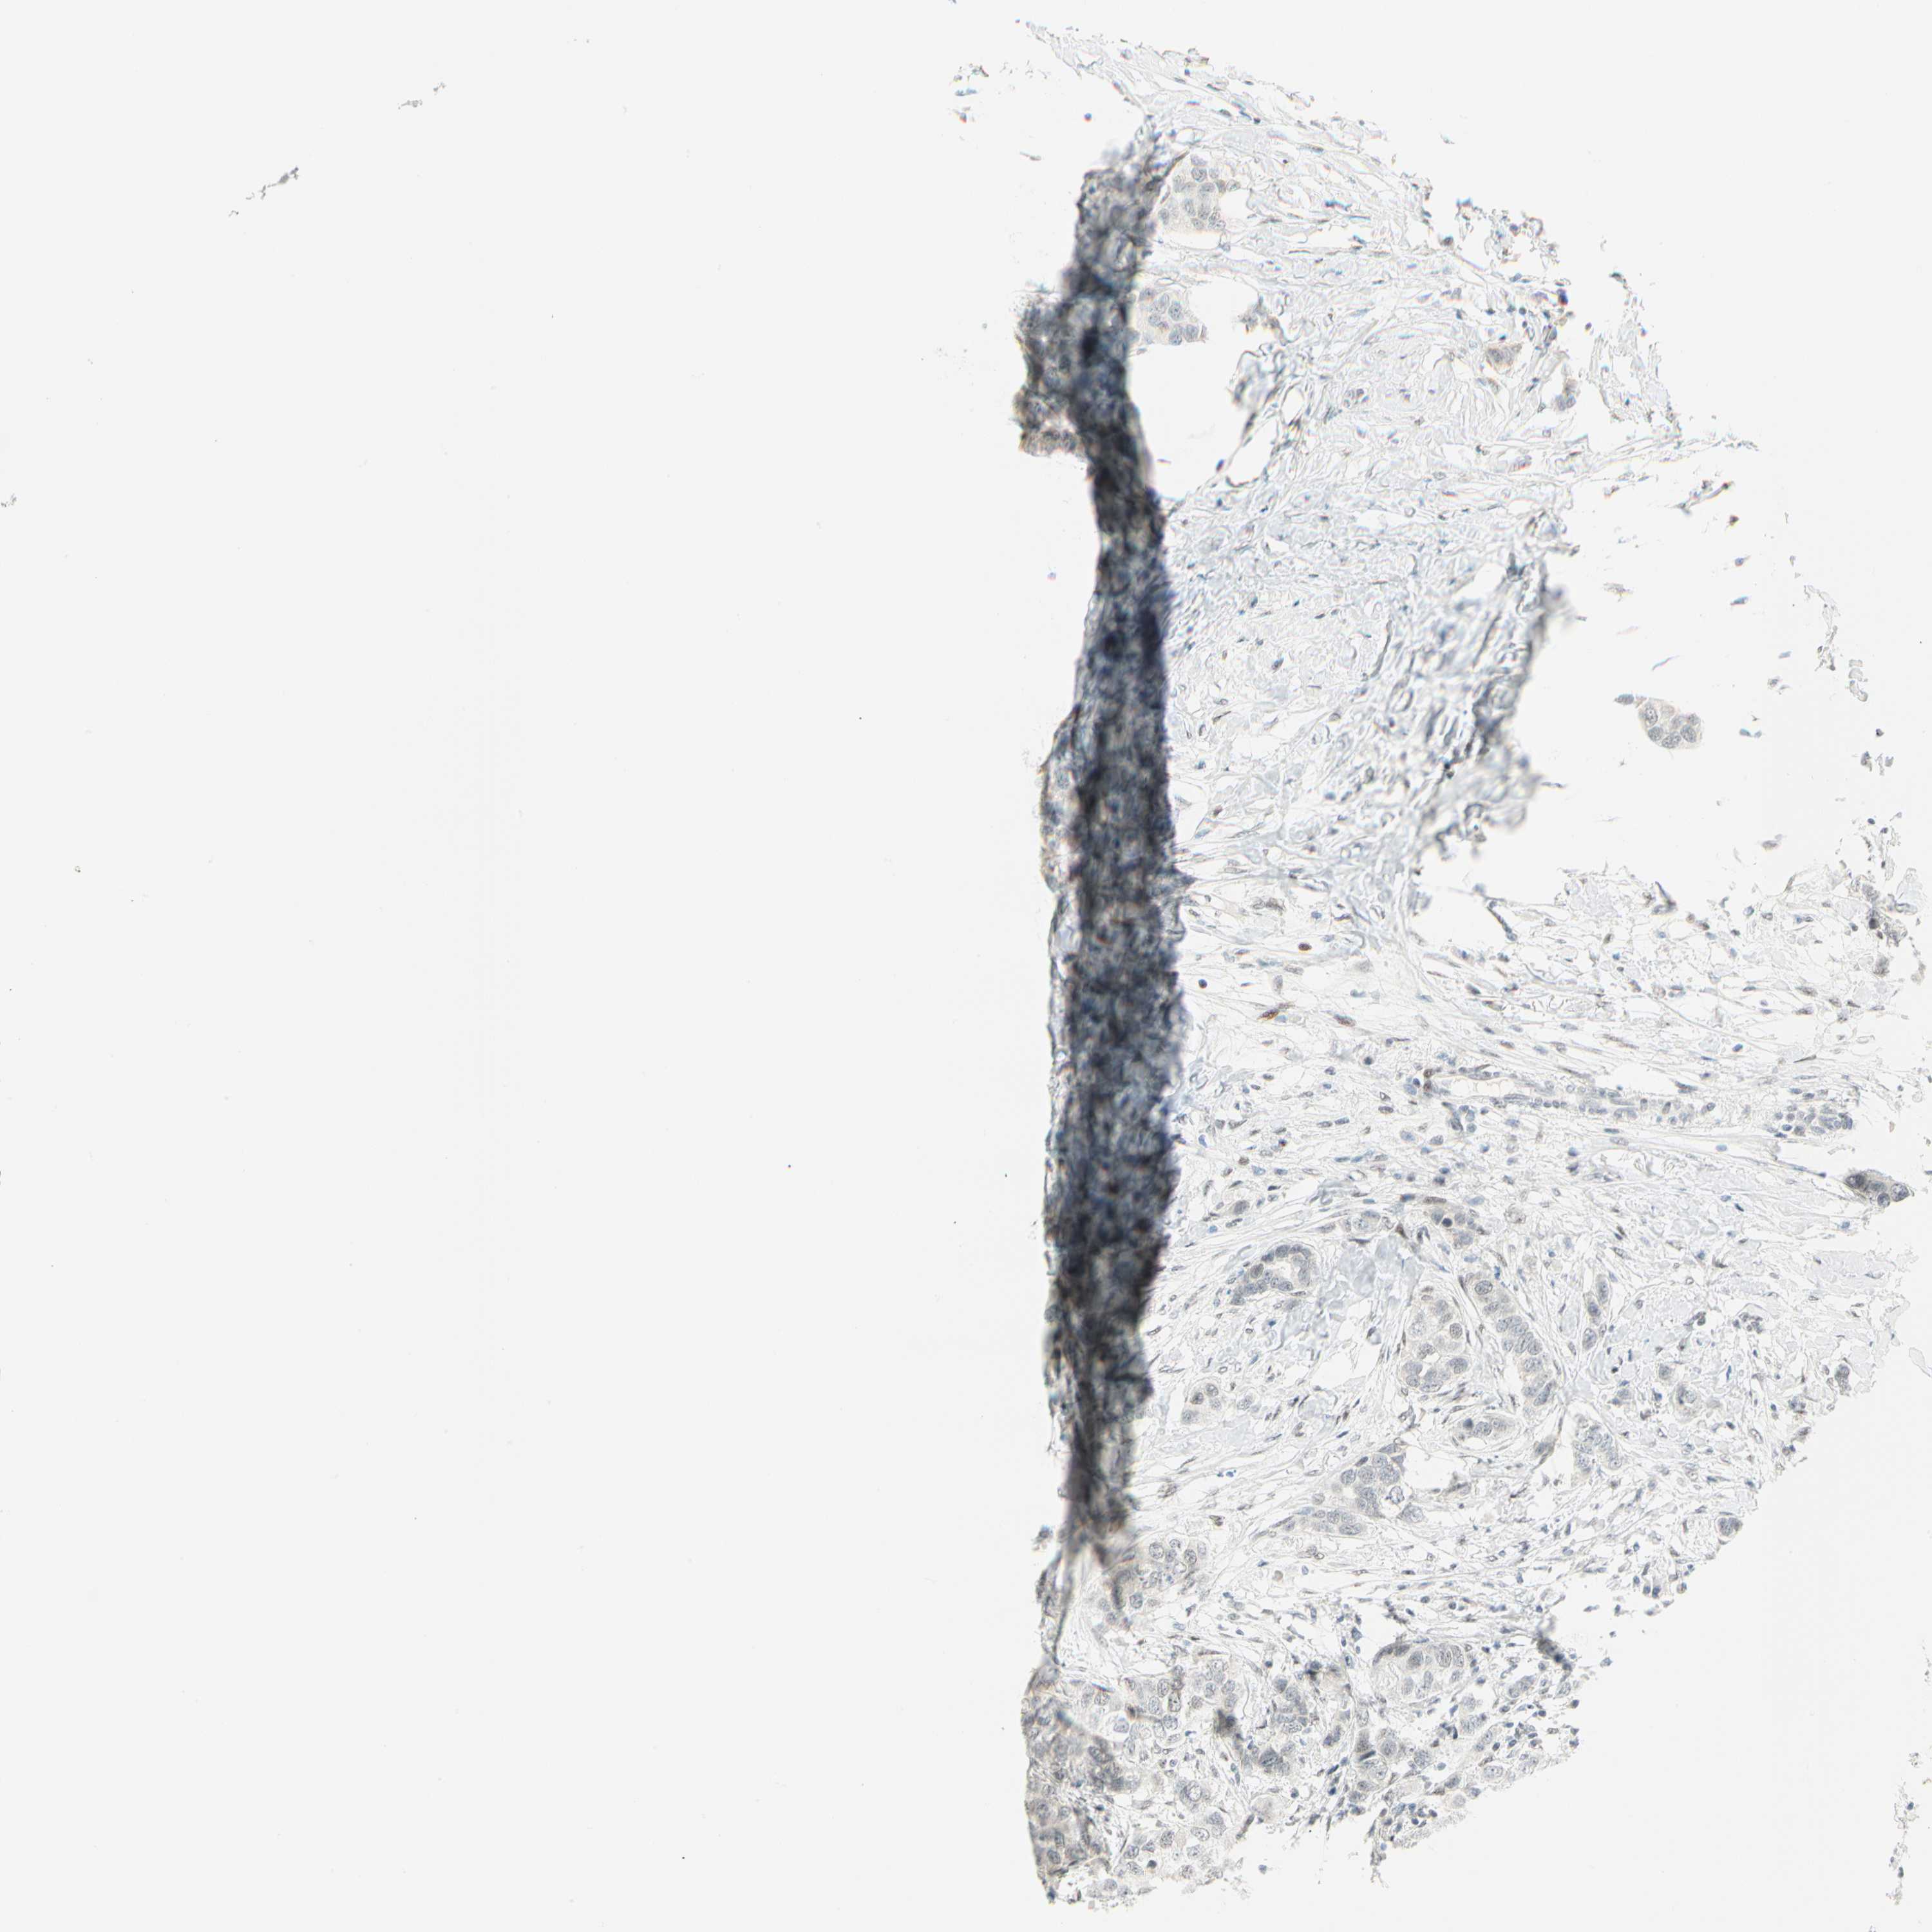

CANCER BREAST CANCER Show tissue menu

BRCA TCGA BRCA VALIDATION PROTEIN EXPRESSION